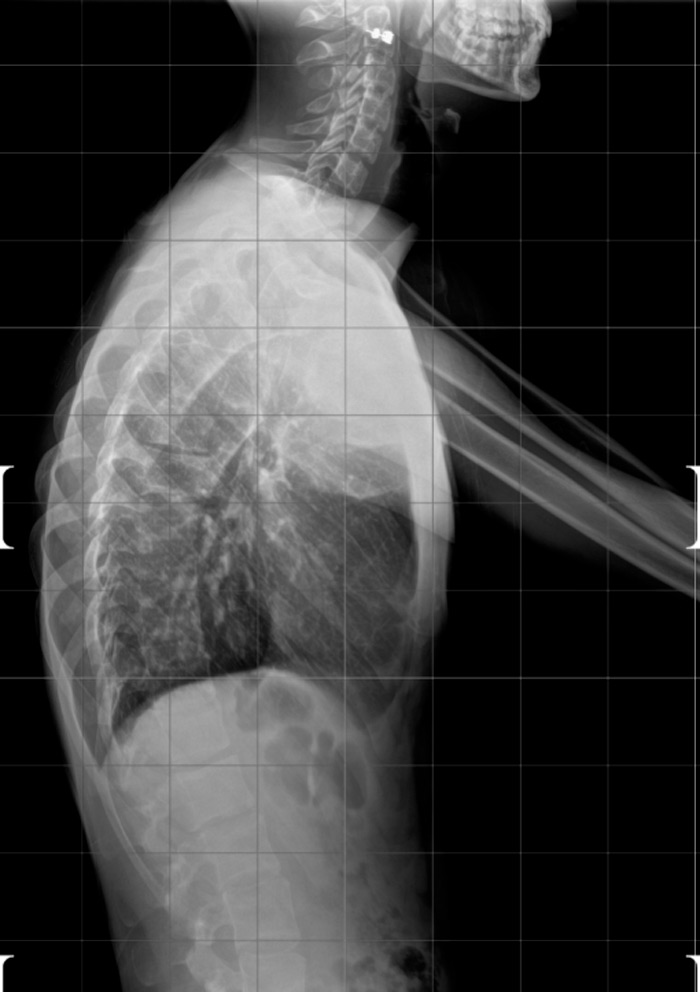

DIAGNOSI:

IPERCIFOSI DORSALE GRAVE

Radiografia dorsale pre operatoria

Intervento chirurgico eseguito:

STABILIZZAZIONE DORSO – LOMBARE CON OSTEOTOMIE CORRETTIVE

Radiografia dorsale post-operatoria